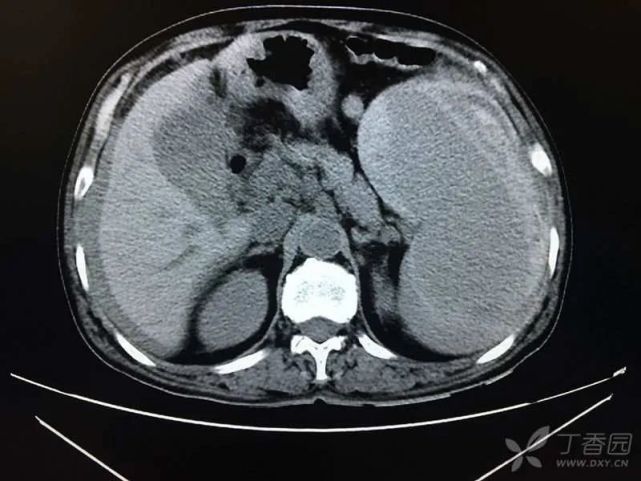

2016 年 2 月患者因「腹胀腹痛 3 d」入住我院普外科。查上腹部 CT 示:脾大、脾破裂、腹腔积液、积血(图 5)。行脾切除术,术后恢复顺利,很快出院。住院期间首次发现肝酶升高:生物化学:ALT 22 U/L,AST 28 U/L,ALP 190 U/L,GGT 323 U/L,TBil 6.6 μmol/L,DBil 2.7 μmol/L,CREA:66 μmol/L。

图片

(图 5 上腹部 CT 图)